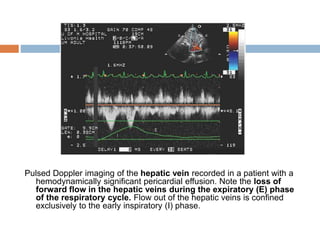

Pulsed Doppler imaging of the hepatic vein recorded in a patient with a

hemodynamically significant pericardial effusion. Note the loss of

forward flow in the hepatic veins during the expiratory (E) phase

of the respiratory cycle. Flow out of the hepatic veins is confined

exclusively to the early inspiratory (I) phase.